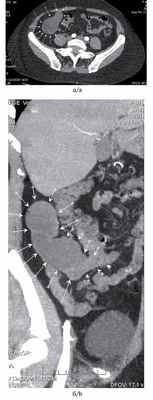

В клинике факультетской хирургии им. Н.Н. Бурденко находилась на обследовании и хирургическом лечении пациентка А., 42 лет, с жалобами на постоянную тянущую боль в правой подвздошной области. Из анамнеза известно, что в течение 4 лет периодически возникали приступы интенсивной боли в правой подвздошной области, в связи с чем неоднократно была госпитализирована в лечебные учреждения по месту жительства, где при обследовании диагностировали хронический аппендицит и проводили консервативную терапию. Последнее ухудшение самочувствия отметила в течение последнего месяца, когда вновь появилась приступообразная боль в правой подвздошной области, что послужило причиной обращения в поликлинику по месту жительства. При УЗИ органов брюшной полости в за брюшинном, субренальном, паракавальном пространствах определено многокамерное жидкостное с хлопьевидным содержимым образование размером 100×38×40 мм, органная принадлежность которого была неясна. Пациентку госпитализировали в нашу клинику, при осмотре живот правильной формы, не вздут, равномерно участвует в акте дыхания всеми отделами, при пальпации мягкий, умеренно болезненный в правой подвздошной области, где при глубокой пальпации определяется объемное образование размером до 15 см. Перитонеальных симптомов нет. Стул регулярный, оформленный, без патологических примесей. Температура тела нормальная, лабораторные показатели в пределах референсных значений. МСКТ органов брюшной полости с внутривенным контрастированием: в области червеобразного отростка, прилегая к куполу слепой кишки, определяется объемное образование с четкими контурами, жидкостной плотности, размером 120×47×43 мм, не накапливающее контрастный препарат (рис. 1, а, Рис. 1. Компьютерная томограмма пациентки А. с цистаденомой червеобразного отростка (указана стрелками). а — сагиттальный срез; б — фронтальный срез. б). Окружающая клетчатка не инфильтрирована, перифокально жидкостные скопления не определяются. Лимфаденопатии на уровнях сканирования не выявлено. На основании анамнеза и результатов проведенного обследования поставлен предварительный диагноз: мукоцеле червеобразного отростка.

Компьютерная томография органов брюшной полости до и после внутривенного введения 40 мл ультрависта: в правой подвздошной области определяется образование неправильной формы размером 12,4 х 5,9 см с ровными контурами, плотностью 33-35 ед, без изменения после введения контрастного вещества (рис. 1). Структура образования неоднородная, с наличием точечных и тяжистых включений, прослеживается тонкая капсула, местами утолщенная и уплотненная, с наличием кальцинации по задней стенке. Верхний полюс образования располагается в илеоцекальном углу, спереди оно прилежит к передней брюшной стенке, медиально - к сигмовидной кишке, сзади - к m.iliacus и правым общим подвздошным сосудам, внизу - спускается в виде ножки в малый таз, плотно прилегая к стенке прямой кишки и мочевого пузыря. Признаков поражения указанных органов не выявлено. Образование подвижно, при сравнении с данными ранее проведенного КТ-исследования отмечается изменение формы и положения. Увеличенных лимфатических узлов в подвздошной области и забрюшинно не выявлено.

Рис. 1. Мукоцеле червеобразного отростка. Компьютерная томограмма.